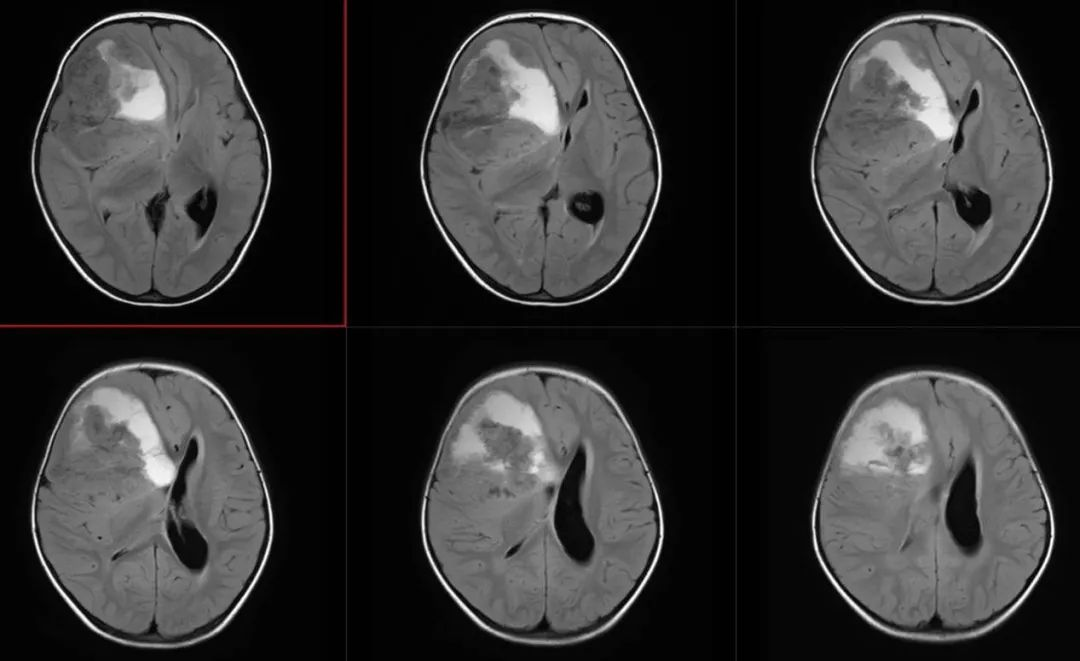

术前FLAIR